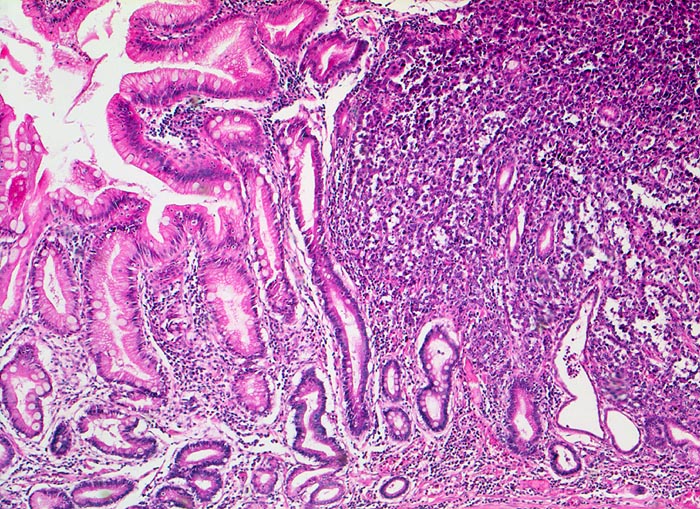

Magenfrühkarzinom

Magenantrum

Links im Bild die Magenschleimhaut mit intestinaler Metaplasie (zahlreiche Becherzellen). Diffuse Tumorinfiltration mit Verdrängung und Umwachsung der ortsständigen Magendrüsen rechts im Bild. Der abgebildete Karzinomanteil ist gering differenziert. Die hochgradig atypischen Tumorzellen bilden nur andeutungsweise erkennbare Drüsenschläuche.

Endoskopische Kontrolle bei Patient mit bekannter chronischer Gastritis.